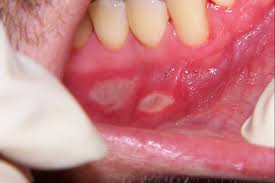

11. The correct answer is D. Why the exact etiology of aphthous ulcers is not clear, there are several conditions that have been tied to triggering them. They include the following: stress, lack of sleep, mechanical trauma, deficiency of B Vitamins, iron deficiency, folic acid deficiency, certain foods like chocolate, and certain times of menstrual cycle.

11. Which of the following has been known to trigger outbreaks of the condition demonstrated below in the photograph below?

A. Nutritional Deficiencies

B. Direct trauma

C. Menstrual Cycle

D. Penicillin